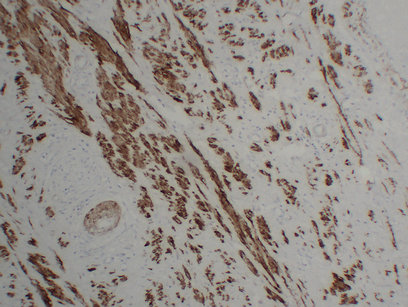

ARG66482 anti-Calponin 1 antibody IHC-P image

Immunohistochemistry: Paraffin-embedded Human squamous carcinoma of the cervix stained with ARG66482 anti-Calponin 1 antibody at 1:200 (4°C, overnight). Antigen Retrieval: Citric acid buffer (pH 6.0) was used.